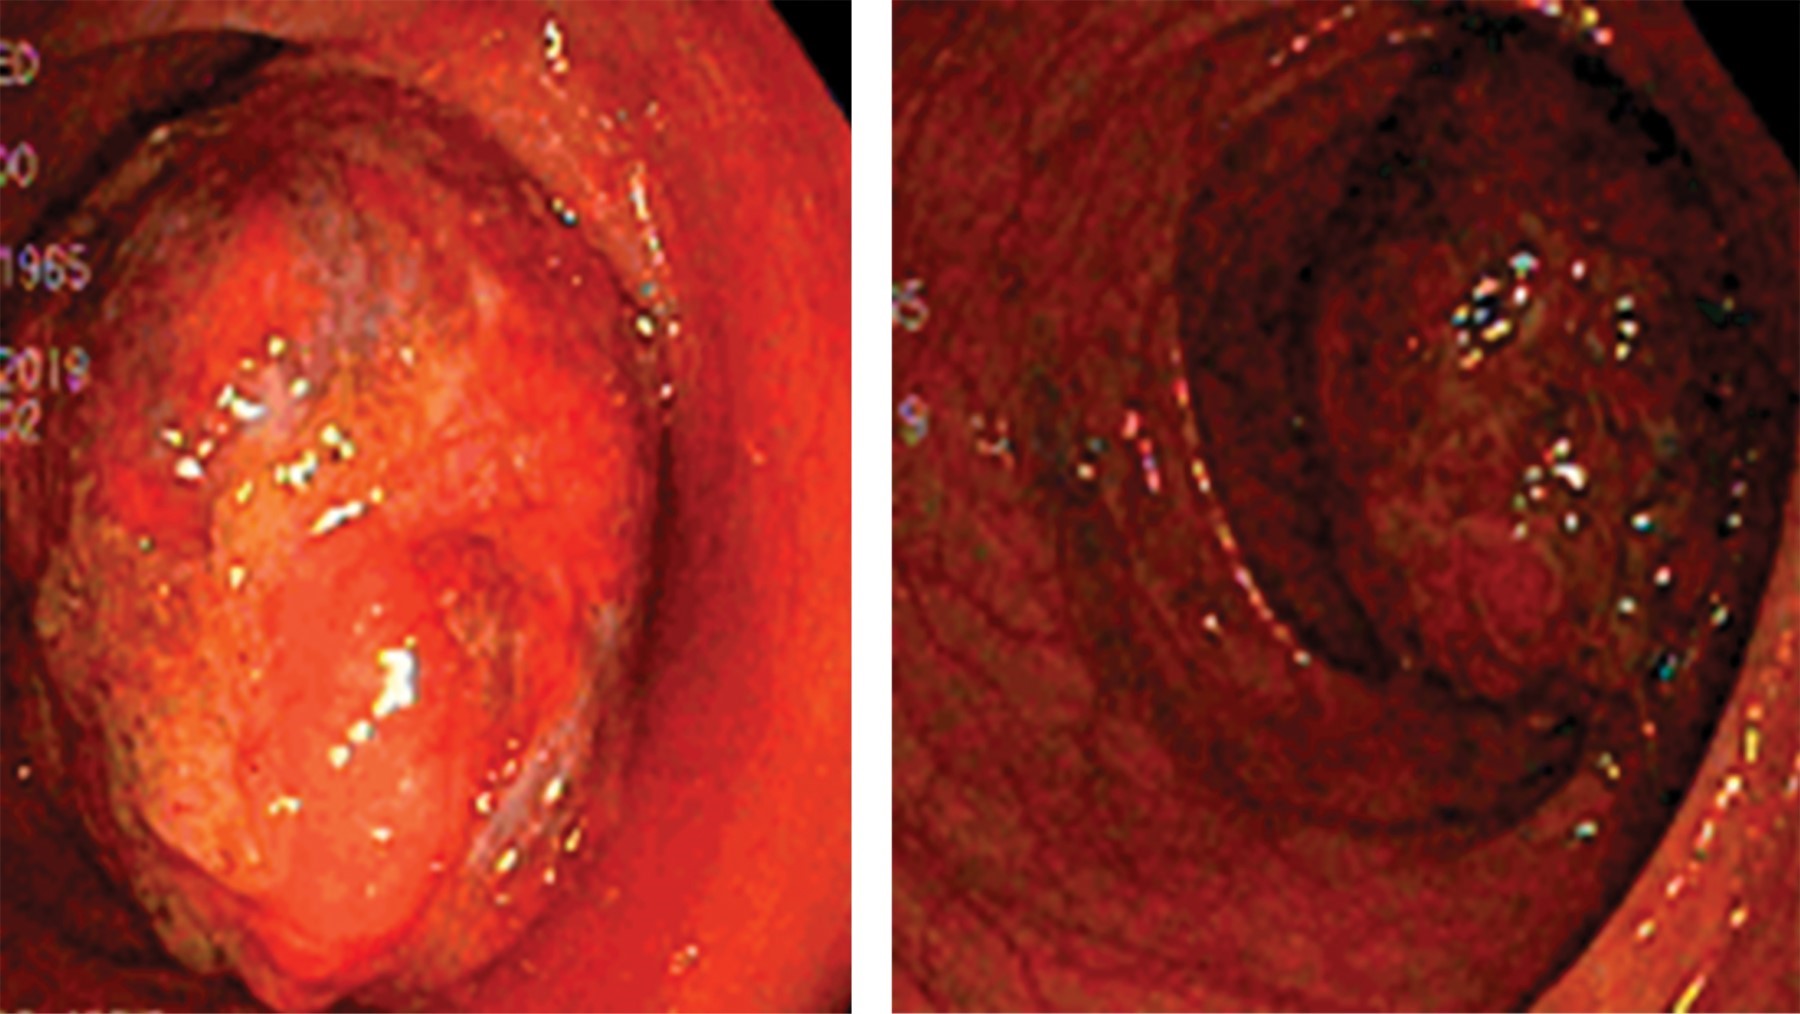

Colonoscopy was performed and a polypoid, spherical tumor was observed, with a broad base, ulcerated in its visible portion, occluding 80% of the intestinal lumen in the transverse colon segment (Figure 2). The rest of the study showed no alterations. Biopsies of the lesion were reported as inflammatory tissue and mucinous material.

Colonoscopy may be both diagnostic and therapeutic since it indicates the site of the lesion, and in specific cases, a loop resection (cold or hot, according to the surgeon's preference) can be performed in lesions smaller than 2 cm or pedunculated.13 In the case presented, resection was not possible due to the size of the lipoma and the wide base, conditions that increase the risk of perforation. Although endoscopic biopsy may not be very useful due to the little information it provides, the formation of ulcerations should always make suspect a malignant pathology,14,15 so the endoscopic or surgical specimen will always be sent to pathology to rule out the latter diagnosis.

Figure 2